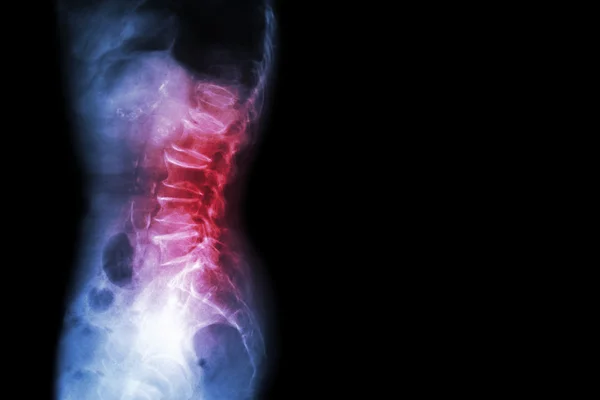

Imaging helps doctors see how much the vertebra has slipped and whether nerves are affected:

- X-rays: Show the alignment of vertebrae and help identify slippage.

- MRI (Magnetic Resonance Imaging): Reveals nerve compression and soft tissue issues.

- CT Scan (Computed Tomography): Offers a detailed look at the bones and spinal canal.